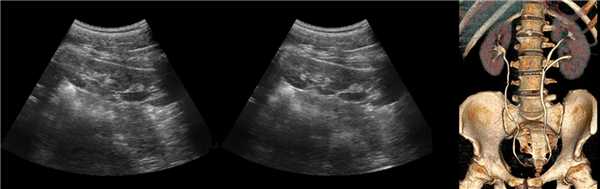

За период с 02.11.2015 г. по 25.04.2016 г. было выполнено 205 УЗИ почечных трансплантатов у 85 пациентов, средний возраст которых составил 38,2±2,1 года. Сроки проведения УЗИ от 0 суток до 10 лет после трансплантации почки. УЗИ проводилось на аппарате Aixplorer (SuperSonic Imagine S.A., Aixen-Provence, Франция), с применением конвексного датчика 1-6 МГц. Исследование проводилось в РКБ МЗ РТ. При оценке состояния трансплантата нами определялись контуры почки, однородность и эхогенность паренхимы, состояние почечного синуса, чашечно-лоханочной системы и мочеточника. При топометрии устанавливались размеры (длина, ширина и толщина) почечного трансплантата. Оценка состояния околопочечного пространства сводилась к поиску свободной жидкости вокруг трансплантата, которая может наблюдаться при образовании гематом, урином и лимфоцеле. В режимах цветовой и спектральной допплерографии был оценен кровоток в сосудах почечного трансплантата, включая сосудистый анастомоз. Определялись систолическая, диастолическая скорости кровотока и индексы резистентности в сегментарных, дуговых и междольковых артериях. При режиме УЭСВ оценивалась жесткость паренхимы на верхнем, нижнем полюсе, латеральном и медиальном крае почечного трансплантата. Для сравнительного анализа, все результаты исследования были разделены на две группы: первая группа ― пациенты на сроках от 0-30 суток после пересадки почки, вторая ― пациенты на сроках более 30 суток после операции. Основной причиной, приведшей к хронической почечной недостаточности (ХПН), у пациентов, перенесших трансплантацию почки, являлся хронический гломерулонефрит.

Клинический пример из первой группы. Пациент М., с хронической почечной недостаточностью. Трансплантация почки произведена от живого родственного донора. Трансплантат находится в правой подвздошной области. При нормальном функциональном состоянии трансплантата, показатели цветовой и спектральной допплерографии оценивались как удовлетворительные, с индексом резистентности не более 0,60 (рис. 1); показатели жесткости паренхимы почечного трансплантата при УЭСВ на различных участках составили от 20,05 до 29,18 кПа (рис. 2-4).

Клинический пример из второй группы. Пациент К. перенес операцию пересадки почки от живого родственного донора. Трансплантат в левой подвздошной области. Индекс резистентности в междольковых артериях составил 0,70 (рис. 5). В сегментарных артериях индекс резистентности составил 0,66 (рис. 6). Показатели жесткости паренхимы почечного трансплантата при режиме УЭСВ составили от 31,6 до 36,9 кПа (рис. 7-9).